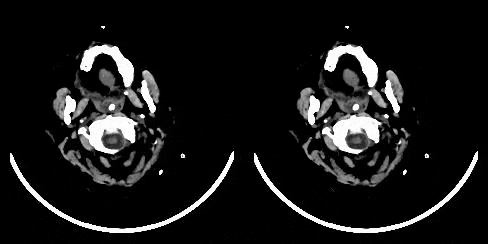

Descrevemos uma abordagem de aprendizado profundo para detecção automatizada de hemorragia cerebral a partir de exames de tomografia computadorizada (TC). Nosso modelo emula o procedimento seguido pelos radiologistas para analisar uma tomografia computadorizada 3D no mundo real. Semelhante aos radiologistas, o modelo examina cortes transversais 2D enquanto presta muita atenção às possíveis regiões hemorrágicas. Além disso, o modelo utiliza o contexto 3D de fatias vizinhas para melhorar as previsões em cada fatia e, posteriormente, agrega as previsões em nível de fatia para fornecer o diagnóstico em nível de tomografia computadorizada. Nós nos referimos à nossa abordagem proposta como Recurrent Attention DenseNet (RadNet), pois ela emprega a arquitetura DenseNet original, além de adicionar os componentes de atenção para previsões em nível de fatia e a camada de rede neural recorrente para incorporar o contexto 3D. O desempenho real do RadNet foi comparado com análises independentes realizadas por três radiologistas seniores para 77 tomografias computadorizadas cerebrais. O RadNet demonstra uma precisão de previsão de hemorragia de 81,82% em nível de tomografia computadorizada, comparável à dos radiologistas. Além disso, o RadNet alcança um maior recall do que dois dos três radiologistas, o que é notável.

RadNet, nossa arquitetura proposta para detectar hemorragia cerebral, emula radiologistas que tentam detectar hemorragias no cérebro deslizando/para cima entre fatias de tomografia computadorizada, tratando a detecção de hemorragia como um problema de modelagem de sequência em que os elementos das sequências são fatias de tomografia computadorizada 2D. Um Dense Convnet com atenção é usado para deduzir coisas em um nível de fatia e um LSTM é então usado para classificar uma sequência de fatias. Quando avaliado contra radiologistas, o RadNet teve um desempenho comparável ao dos radiologistas e uma pontuação F1 melhor do que eles.